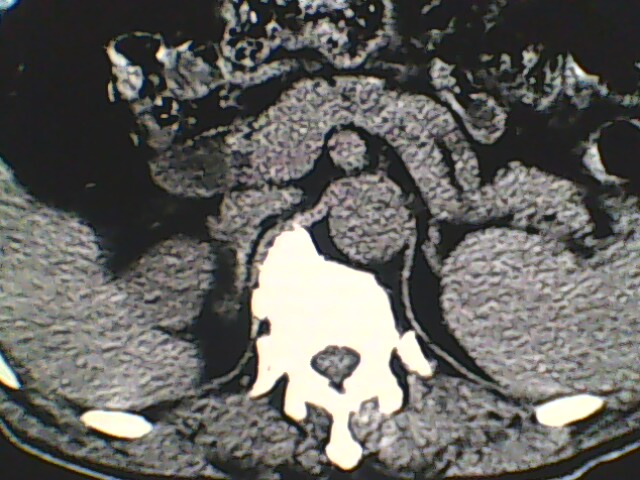

男,56岁,高血压,临床怀疑肾上腺问题,肝脏怎么那么高啊?能描述一下么?

右侧膈膨升,间位结肠,胸腰椎退行性骨关节病,右侧肾上腺可疑增生(图像颗粒太粗,窗太窄,不好看)。

支持 右侧膈膨升,间位结肠;胸腰椎退行性骨关节病;双侧肾上腺可疑增生。